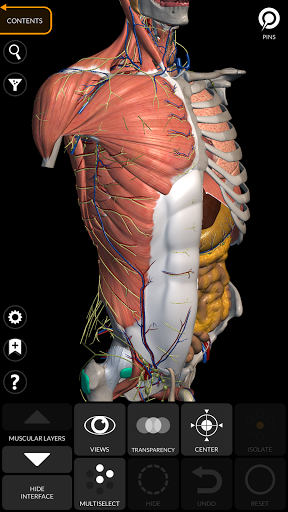

يتيح لك "Anatomy 3D Atlas" دراسة التشريح البشري بطريقة سهلة وتفاعلية.

من خلال واجهة بسيطة وبديهية، من الممكن ملاحظة كل بنية تشريحية من أي زاوية.

تتميز النماذج التشريحية ثلاثية الأبعاد بتفاصيل خاصة ودقة تصل إلى 4K.

يسهل التقسيم حسب المناطق والمناظر المحددة مسبقًا مراقبة ودراسة الأجزاء الفردية أو مجموعات الأنظمة والعلاقات بين الأعضاء المختلفة.

نماذج تشريحية ثلاثية الأبعاد

• الجهاز العضلي الهيكلي

• تصور العضلات من خلال مستويات الطبقات من الطبقات السطحية إلى الأعمق